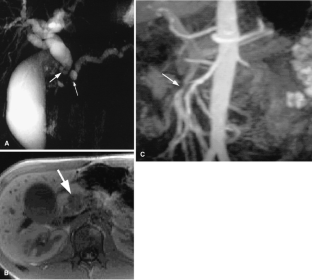

Usual and unusual causes of extrahepatic cholestasis: assessment with magnetic resonance cholangiography and fast MRI

Cholestasis may result from hepatocellular (intrahepatic) disease or biliary tract (extrahepatic) abnormalities. Etiologies causing extrahepatic cholestasis are extremely diverse and invasive procedures, such as endoscopic retrograde cholangiopancreatography (ERCP) and percutaneous transhepatic cholangiography (PTC), were previously required to establish the diagnosis. Due to refinements of magnetic resonance imaging (MRI) techniques, the patient with extrahepatic cholestasis currently can be evaluated noninvasively, and the information revealed frequently exceeds the findings obtained by ERCP and PTC. In this essay, we illustrate the classic MR cholangiographic (MRC) and MRI features of a variety of disorders causing extrahepatic cholestasis, including non-neoplastic disorders of the biliary tract (congenital abnormalities, infectious processes, iatrogenic disorders, and postsurgical complications) and neoplastic conditions (e.g., tumors of the pancreas, biliary tree, liver, ampulla, and regional lymph nodes). In most cases, familiarity with the key MRC features in addition to information obtained via cross-sectional MR images provide sufficient information for adequate lesion characterization.